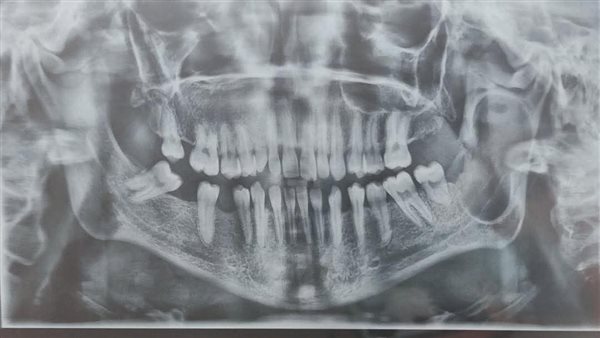

حيث نجح فريق جراحة التجميل بمستشفى دمياط العام في إجراء جراحة دقيقة لاستئصال ورم بالفك السفلي لمريض كان يعاني من آلام حادة وتورم مؤثر على وظائف الفم، حيث تمكن الفريق من إزالة الورم بالكامل بطريقة جراحية دقيقة مع أخذ عينة من النسيج المستأصل لإرسالها إلى قسم الباثولوجي لإجراء التحليل المعملي اللازم وتحديد طبيعة الورم بشكل دقيق.

ولم يقف النجاح عند حدود الاستئصال، بل واصل الفريق الطبي جهوده للحفاظ على الشكل الجمالي والوظيفي للفك، حيث تمت إعادة البناء باستخدام بديل عظام (Bone Substitute) بما يضمن للمريض القدرة على استعادة وظائف الفك الطبيعية، مع الحفاظ على الشكل الخارجي دون تشوهات، وهو ما يُعد خطوة مهمة في هذا النوع من الجراحات المعقدة التي تتطلب خبرة دقيقة وتنسيقا عاليا بين جراحي التجميل وفريق التخدير.